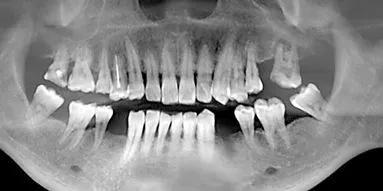

影像學檢查

種植手術將種植體(ti) 植入牙槽骨中,其成功的關(guan) 鍵在於(yu) 種植體(ti) 與(yu) 周圍牙槽骨是否形成骨結合,因此對骨質及骨量的正確評估十分必要。缺牙區牙槽骨因長期廢用而萎縮,除口內(nei) 檢查缺牙區牙槽脊高度及寬度外,攝X線片及錐束CT可觀察缺牙區骨質密度,可用骨高度及寬度,從(cong) 而評估每個(ge) 患者的種植位點,製定相應手術方案並避免術中損傷(shang) 重要組織結構。